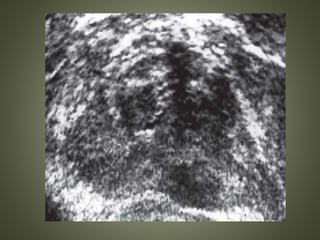

HYPERECHOIC CANCER

• Infrequent

• Due to desmoplastic response of the surrounding

glandular tissue to the presence of the tumor or

to infiltration of neoplasm into a BPH background

with preexisting degenerative calcifications

• Cribriform pattern and comedonecrosis with focal

calcifications

• Calcifications associated with comedonecrosis

are tiny and act as crystals by being highly

echogenic, more so than dystrophic

calcifications.

• On scanning they are conspicuous and appear

to twinkle, giving a “starry sky” appearance.